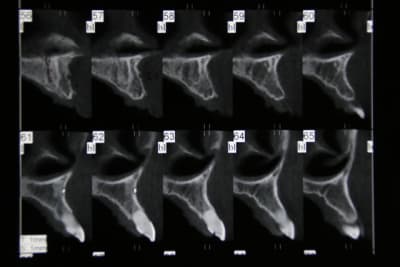

tes coupes, c'est tous les 1 ou 2 mm ?

tes latérales, elles ont des racines comment ? Sur le scan on a une image de racine résorbées

ce sont des coupes de 1mm , j'ai un peu moins de 10mm (sans compter le canal qui fait 2-3 mm de diam). Justement j'envisage d'enlever 22 (la moins fiable) et de poser implant 11-22 + bridge. Et si le patient refuse deux implants 11-21 mais les diam des implants vont vraiment etre faible .... no se